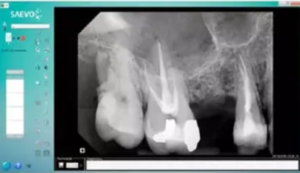

A ideia pode parecer diferente à primeira vista, mas faz todo sentido dentro de ambientes profissionais, especialmente em consultórios e clínicas. O Sensor Digital Odontologico, além de ser um item essencial na rotina odontológica, pode contribuir para transmitir uma imagem de inovação, organização e avanço tecnológico. Quando bem integrado ao espaço, ele deixa de ser apenas um equipamento e passa a compor a identidade visual do ambiente.

A presença de equipamentos modernos reforça a percepção de profissionalismo e cuidado com os detalhes. Um ambiente que evidencia tecnologia transmite confiança e credibilidade, fatores essenciais para conquistar e fidelizar clientes. Incorporar o Sensor Digital Odontologico de forma estratégica na decoração pode ajudar a criar uma atmosfera mais clean, sofisticada e alinhada com tendências contemporâneas.

Mais do que estética, a decoração precisa ser funcional. E nesse ponto, o Sensor Digital Odontologico pode ser um aliado importante. Integrar tecnologia ao design permite otimizar espaços, melhorar fluxos de trabalho e ainda manter uma aparência harmoniosa.